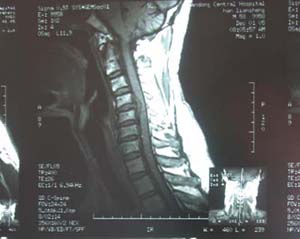

韩连生,男,58岁,双上肢疼痛及四肢不能活动20天,加重10天,颈椎核磁共振片示:颈间盘脱出(C5)颈间盘突出(C6),突出及脱出之间盘部分骨化,入院诊断1、高位截瘫2、颈椎病(脊髓型、C4-6)入院后于全麻下行颈前路C5、C6椎体次全切,椎管扩大,C4-6植骨融合术 ,术后两周围颈托离床活动,三个月摄X线片示:植骨完全融合。患者象发病前一样于单位正常工作。咨询电话:7942354

手术前